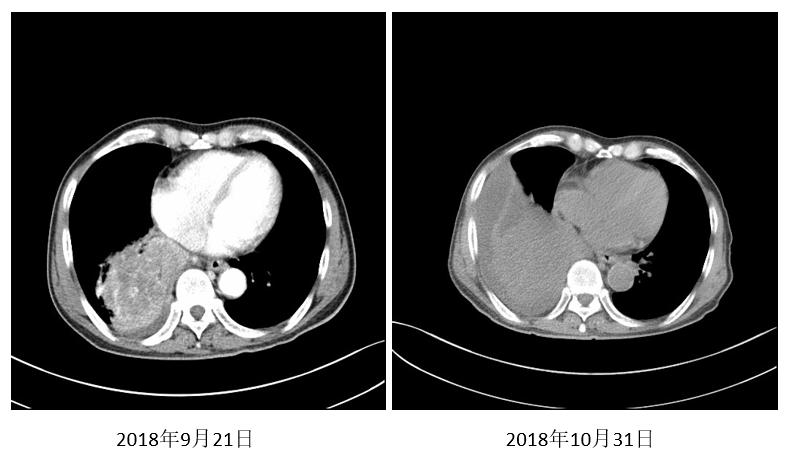

朱某某,男性,69岁。2018年9月因咳嗽、痰中带血伴胸闷不适,检查发现右下肺占位就诊。病理经皮肺穿刺示:鳞癌。诊断为:右下肺鳞癌,临床分期T4NxM0 Ⅲ期,PS评分1分,基因状态未知。

图1. 2018年9月21日首诊CT

2018年10月23日行紫杉醇240mg D1+顺铂 30mg D1-D4方案化疗1周期。出现4度骨髓抑制伴粒缺性发热、胃肠道反应。同时复查胸部CT。

图2. 2018年10月31日复查(粒缺性发热)